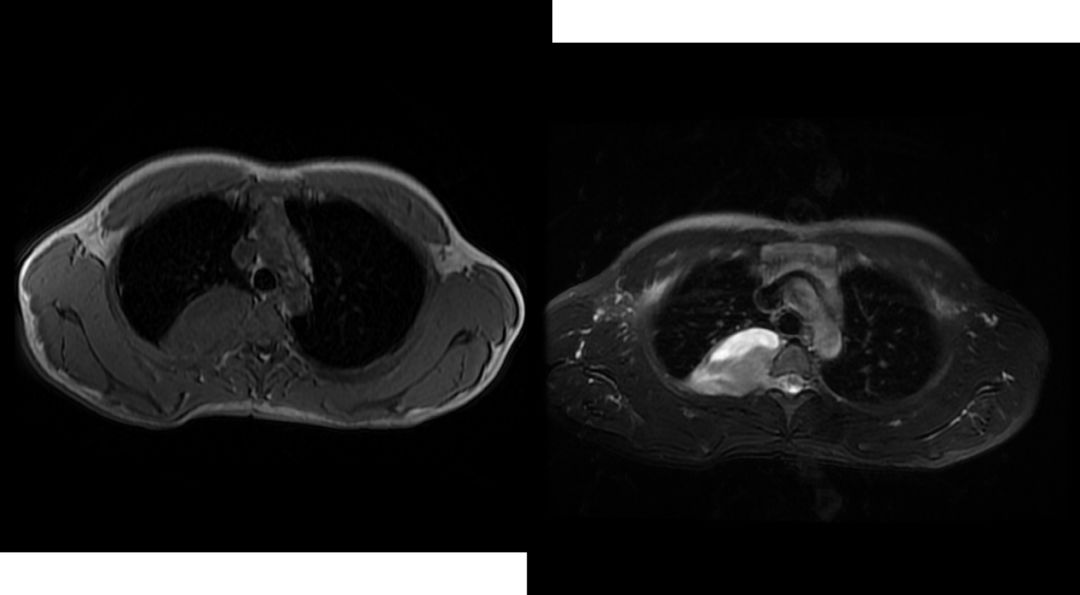

图1胸腺瘤A;图2胸腺瘤AB;图3胸腺瘤B;图4胸腺癌

1.胸腺瘤

胸腺瘤是前纵隔肿瘤最常见的原发性肿瘤,约占50%。

部位:前纵隔中部偏上。

形状:圆形或分叶状实性肿块。

密度:多均匀,可有坏死、钙化。

边缘:良性清楚,病变周围脂肪间隙存在;恶性不清,病变周围脂肪间隙,消失,胸腔及心包可有积液。

增强扫描:实性部分中等强化,坏死区不强化。

组织学分型:A型和AB型为良性肿瘤,B1型为低度恶性,B2型为中度恶性,B3型与胸腺癌均为高度恶性,侵袭性强。